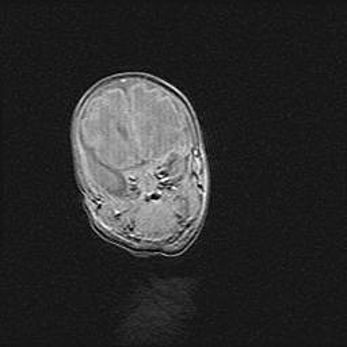

Множественные кисты обоих полушарий головного мозга, наибольшая из них в правой затылочной области. Ассиметричная атрофическая гидроцефалия.

Возраст: 7 месяцев

Вес: 5660 г

Пол: мужской

Окружность головы: 41,5 см

Срок гестации: 28-29 недель

Кисты головного мозга развиваются в результате многоочаговых некрозов вещества мозга и возникают вследствие перенесенной перинатальной инфекции, менингитов, энцефалитов, асфиксии, родовой травмы, расстройств мозгового кровообращения различного генеза. Образованию кист в веществе головного мозга плодов и новорожденных способствуют такие факторы, как высокое содержание в нем воды, недостаточная (или отсутствие) миелинизация и слабая астроглиальная реакция на повреждение.

Кисты могут сочетаться с гидроцефалией и другими поражениями головного мозга.